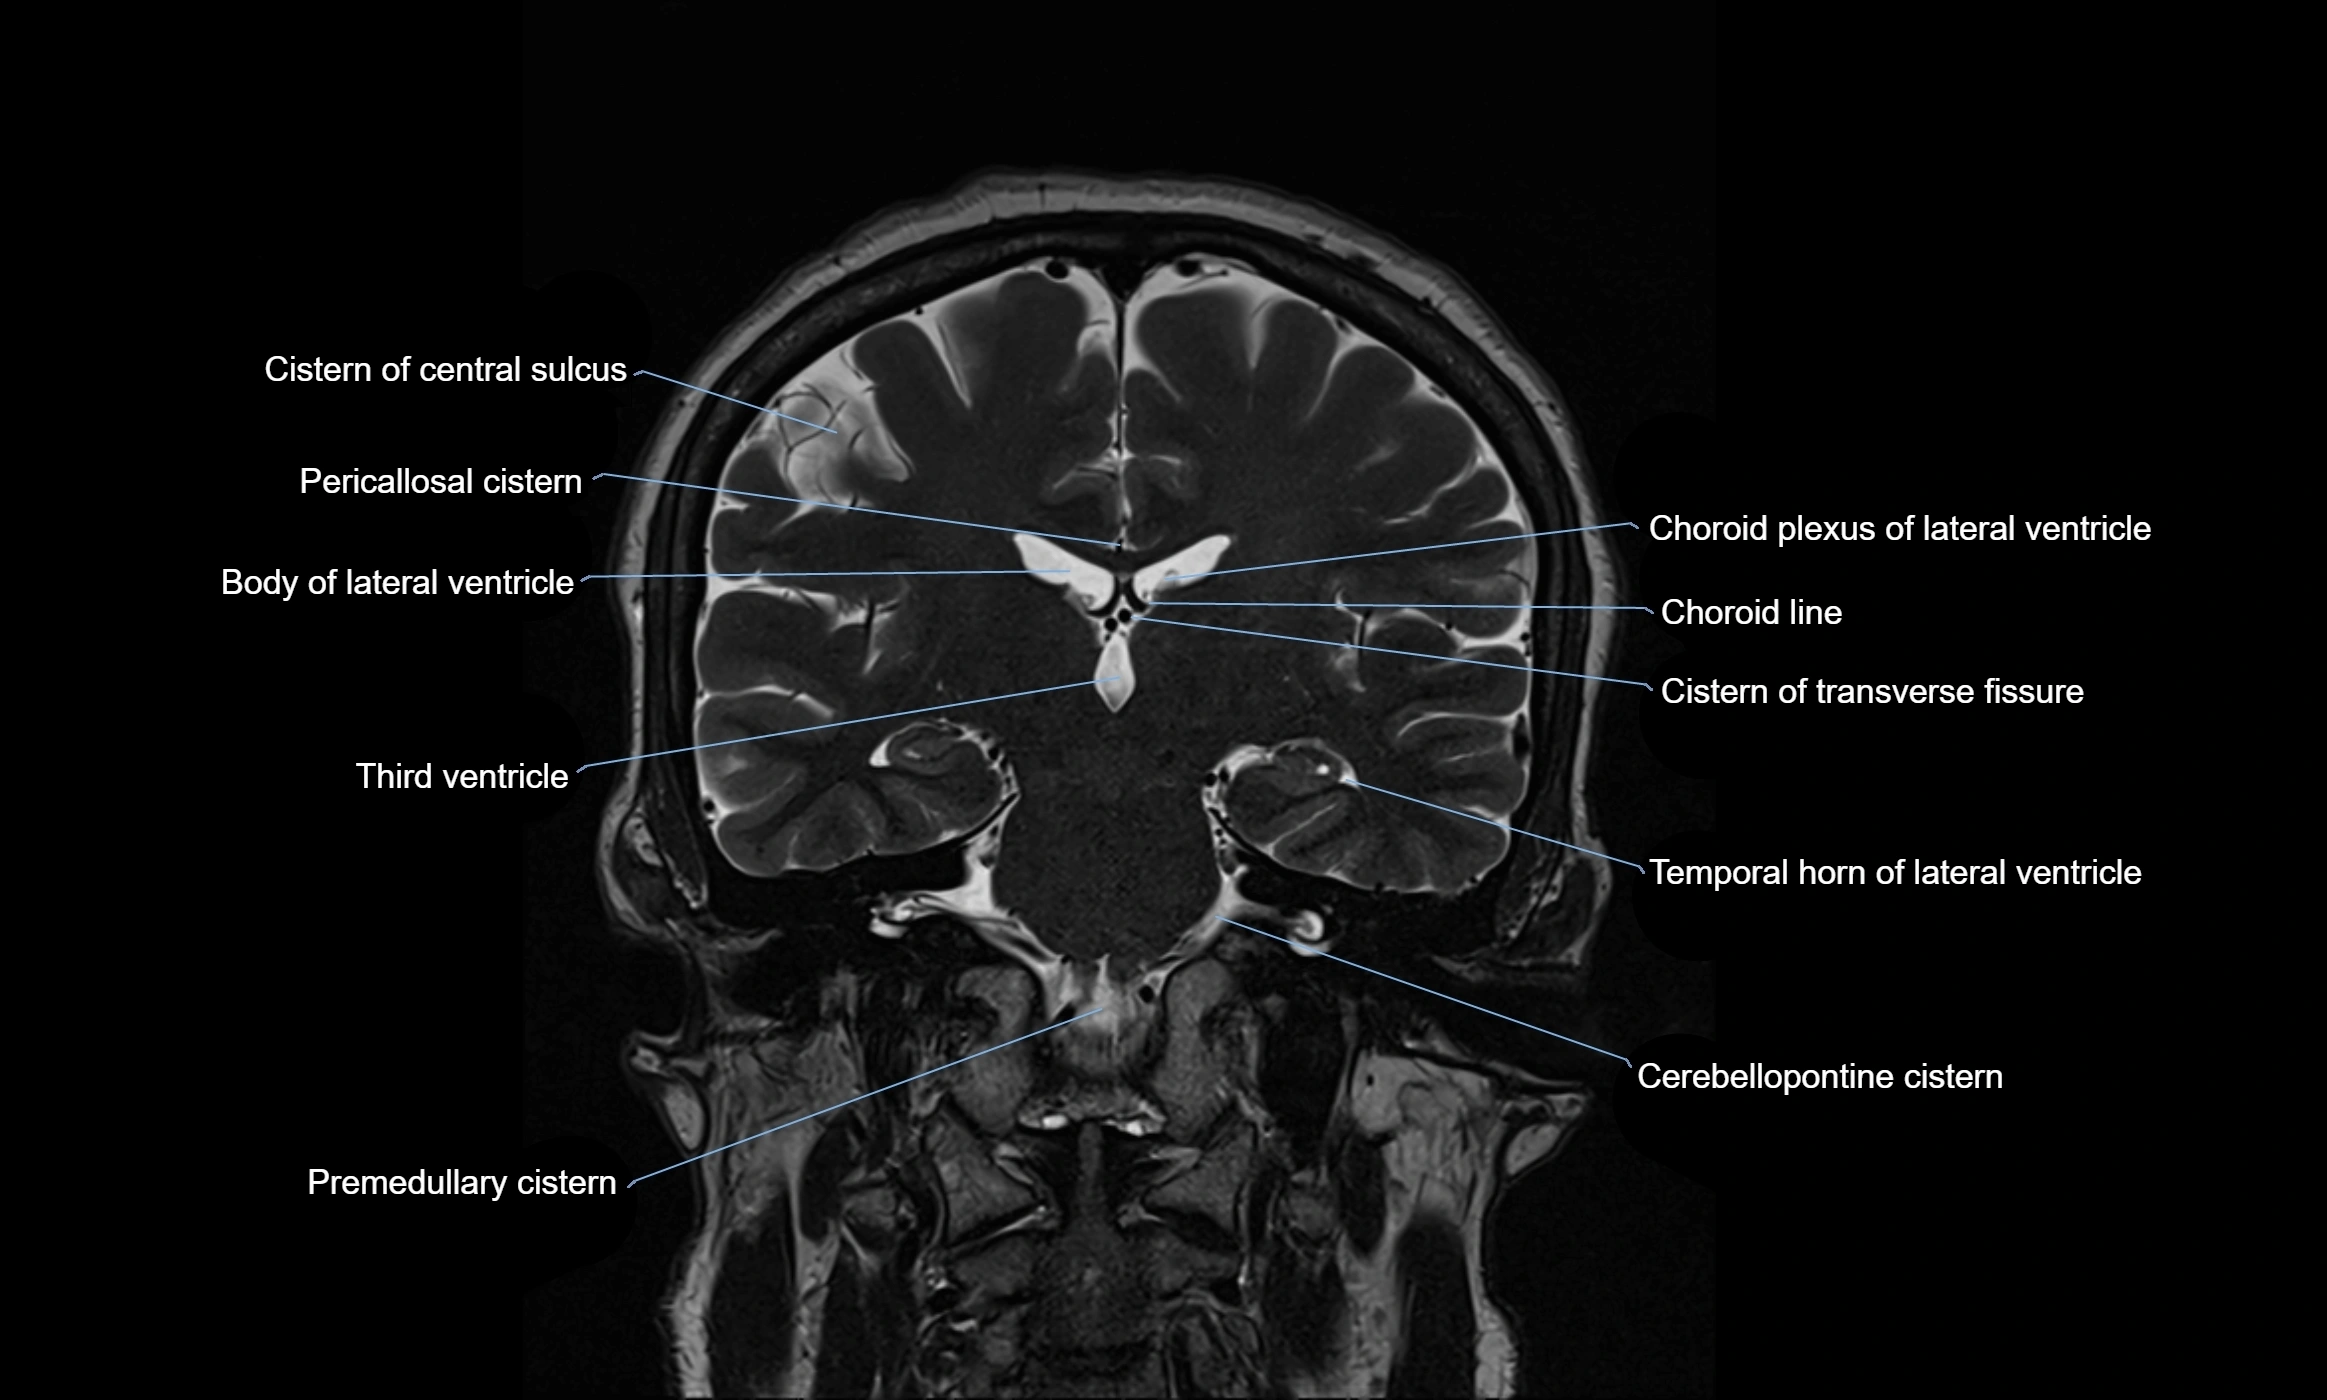

Ambient cistern

The ambient cistern is a paired, narrow, and elongated subarachnoid space located bilaterally along the lateral aspect of the midbrain. It serves as a conduit between the interpeduncular cistern anteriorly and the quadrigeminal cistern posteriorly. This cistern houses critical neurovascular structures, including parts of the posterior cerebral artery, superior cerebellar artery, trochlear nerve (cranial nerve IV), and the basal vein of Rosenthal. It plays an important role in the circulation of cerebrospinal fluid (CSF) and provides an anatomical corridor for various vessels and nerves passing around the midbrain.

MRI Appearance

• T2-weighted images:

• The cistern is hyperintense (bright) due to the high water content of CSF.

• Encapsulated vessels and nerves are seen as flow voids or hypointense lines within the bright background.

MRI images

image